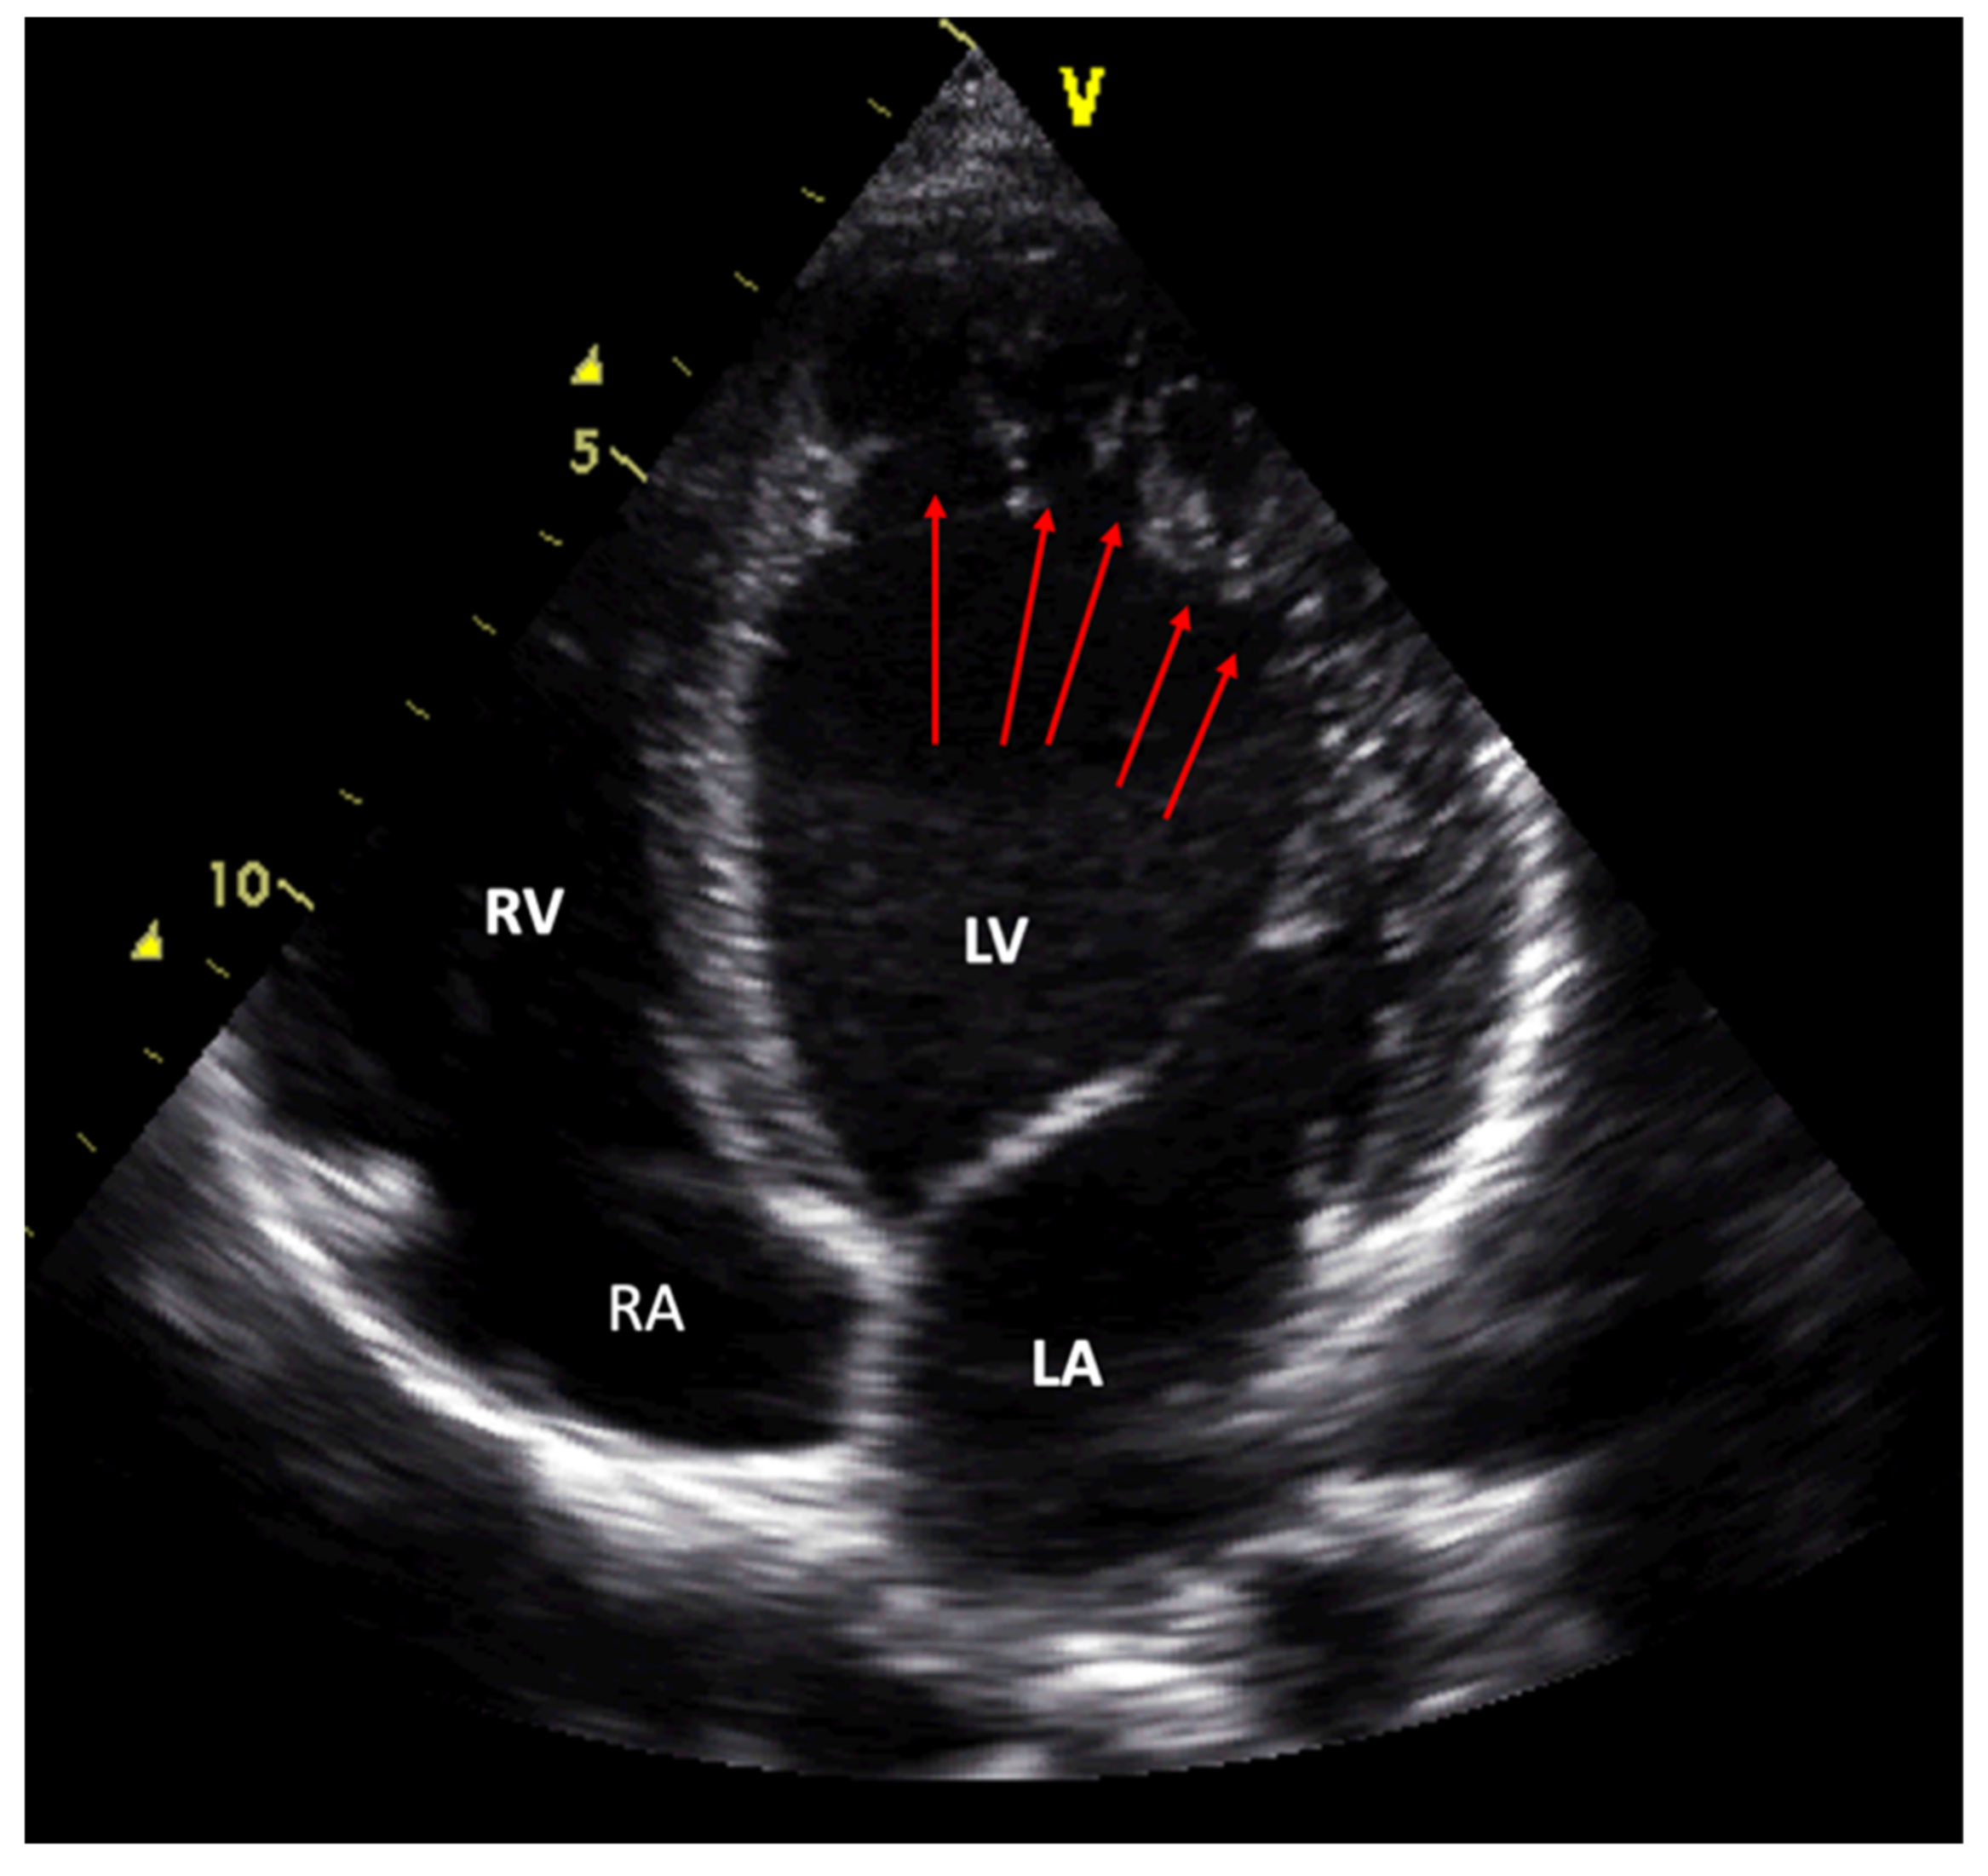

1. At least four prominent trabeculations and deep intertrabecular recesses; |

2. Blood flow between the cavity of the left ventricle and the recesses demonstrable by color Doppler echocardiography or by the use of ultrasonographic contrast medium; |

3. The left ventricular wall segments show a typical bilaminar structure, and the noncompact subendocardial layer is at least twice as thick as the compact subepicardial layer in systole; |

4. No other cardiac abnormalities present. |

| Jenni 2001; [8,78] | Zurich | Excessive prominent trabeculations | Deep intertrabecular recesses | Compacted thin epicardial and much thicker noncompacted endocardial | NC/C > 2 | Abnormalities absent | Perfused recesses in color Doppler | End systole | Short axis view |

| Engberding 2007; [62] | Germany | At least 4 prominent trabeculations | Deep intertrabecular recesses | Bilaminar structure | NC/C ≥ 2 | No other cardiac abnormalities | Blood flow in recesses in color Doppler or with echo contrast | Systole | |